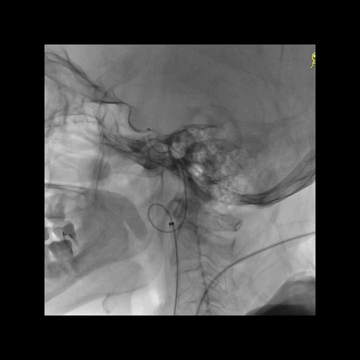

微导丝习惯性进入后交通动脉。

跟进微导管,以及微导丝头端重新塑形后进入M1。

M1远端栓子坚硬,微导丝难以通过;尝试微导管通过,但失败;微导丝头端重新塑形后尝试也未果。

中间管内衬.018"导丝(Command 18),并尽力推高长鞘,在增强支撑下把中间管头端推送至颈内动脉末端,以增加对微导管微导丝的支撑性。